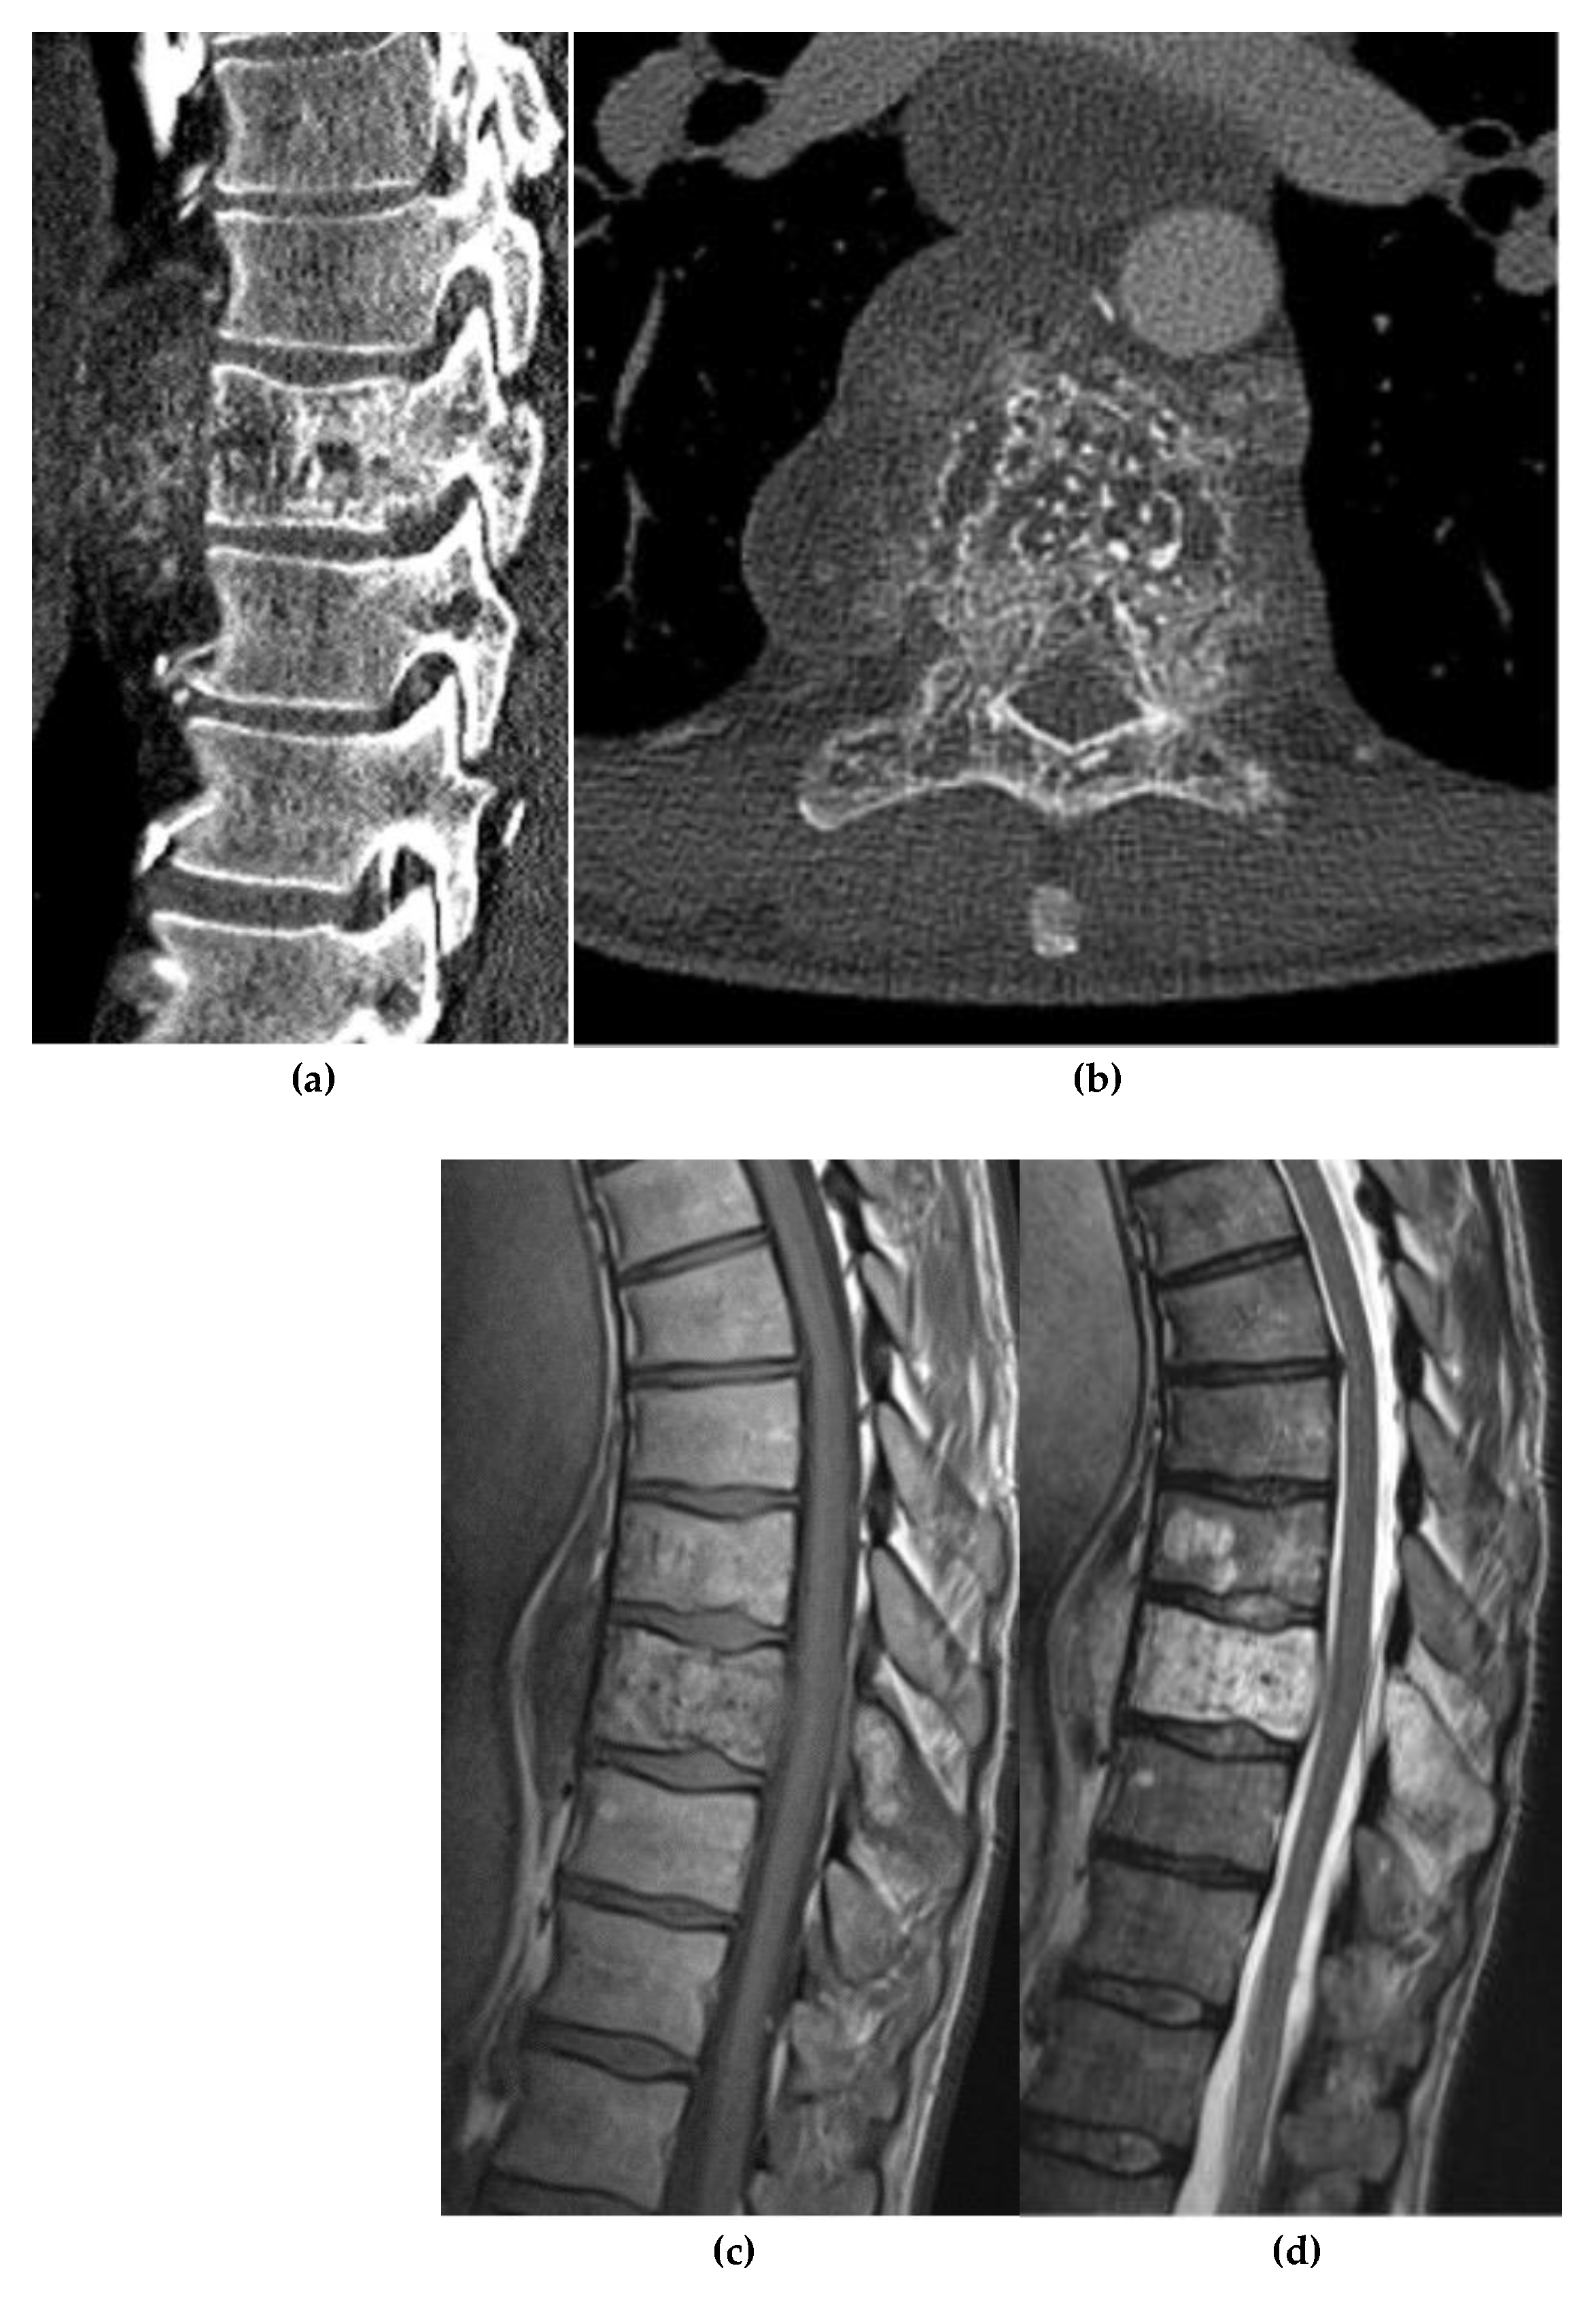

Chondrosarcoma

- Boehme, K. A. , Schleicher, S. B., Traub, F., & Rolauffs, B. Chondrosarcoma: A Rare Misfortune in Aging Human Cartilage? The Role of Stem and Progenitor Cells in Proliferation, Malignant Degeneration and Therapeutic Resistance. Int. J. Mol. Sci. 2018, 19, 311. [Google Scholar] [CrossRef]

- Weinschenk, R. C. , Wang, W.-L., & Lewis, V. O. Chondrosarcoma. J. Am. Acad. Orthop. Surg. 2021, 29, 553–562. [Google Scholar] [CrossRef]

- Kim, J.-H. , & Lee, S. K. Classification of Chondrosarcoma: From Characteristic to Challenging Imaging Findings. Cancers 2023, 15, 1703. [Google Scholar] [CrossRef]

- Katonis, P. , Alpantaki, K., Michail, K., et al. Spinal Chondrosarcoma: A Review. Sarcoma 2011, 2011, 378957. [Google Scholar] [CrossRef]

- Nguyen, T. T. , Thelen, J. C., & Bhatt, A. A. Bone Up on Spinal Osseous Lesions: A Case Review Series. Insights Imaging 2020, 11, 80. [Google Scholar] [CrossRef]

- Ollivier, L. , Vanel, D., & Leclère, J. Imaging of Chondrosarcomas. Cancer Imaging 2003, 4, 36–38. [Google Scholar] [CrossRef]